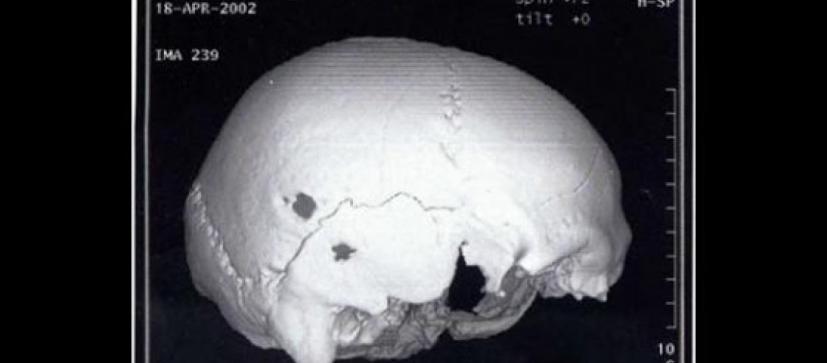

Οι Έλληνες ειδικοί, εξέτασαν το κρανίο σε αξονικό τομογράφο για να μελετήσουν τη δομή του οστού όπου είχε γίνει η επέμβαση. Η οπή είχε σχήμα ωοειδές με διαστάσεις 8 επί 7,5 χιλιοστά και τα άκρα της ήταν κυρτωμένα, υποδεικνύοντας ότι η διαδικασία της επούλωσης είχε ξεκινήσει μετά την επέμβαση.

Ήταν σίγουρα μια πολύωρη επέμβαση και επώδυνη για τον ασθενή, παρά την κατάσταση μέθης που βρισκόταν. Η μορφολογία του σχήματος της οπής, κάνει τους ειδικούς να πιστεύουν ότι η επέμβαση πραγματοποιήθηκε τρίβοντας πάνω στο κρανίο κάποιο λίθινο, κατά πάσα πιθανότητα, εργαλείο.